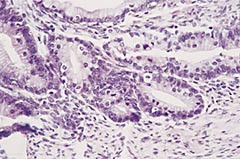

Høyre ovarium var inntatt av en multicystisk tumor som veide 8,2 kg og hadde største diameter på 30 cm. En rekke snitt ble fremført for histologisk undersøkelse. De viste alle mucinøse cyster kledd av atypisk epitel som vokste både kribriformt og papillært (fig 3). Infiltrerende vekst eller kapselgjennombrudd ble ikke sett, og den histologiske diagnosen var atypisk mucinøst cystadenom (borderlinetumor). DNA-måling med væskestrømscytometri og bildeanalyseteknikk viste at svulsten var diploid. Det ble ikke påvist sykelige forandringer i venstre ovarium, uterus, lymfekjertler eller oment. Immunhistokjemisk undersøkelse viste positivitet for B72.3, membranpositivitet for CEA, svak positivitet for E-kadherin, fokal positivitet for BerEP4 og negativitet for CA 125 (tab 1).